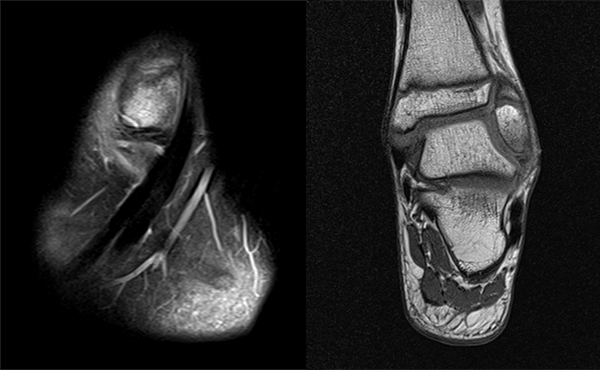

Os subfibulare

Multiple laminäre Ausrisse des fibularen Bandapparats aus der Fibulaspitze können zur Entwicklung eines Os subfibulare führen. Das Os subfibulare findet sich unterhalb der Fibulaspitze ventral der Peronealsehnen. Ohne Schmerzsymptomatik bzw. Aktivierung im MRT hat Das Os subfibulare keinen Krankheitswert. Ein mobiles Os subfibulare führt zu einer lokalen mechanischen Reizung teilweise in Verbindung mit einer Instabilität des Sprunggelenks. Im MRT zeigt sich eine Aktivierung des instabilen Areals. Bei anhaltenden Schmerzen besteht die Behandlung in einer operativen Entfernung des Knochens mit Refixation des Kapselbandapparats.

Os trigonum

Das Os trigonum lässt sich als isolierter Knochen dorsal des Talus seitlichen Röntgenbild darstellen. Normalerweise hat das Os trigonum keine klinische Relevanz. Bei entsprechenden Beschwerden und einer Aktivierung im MRT kann der Knochen arthroskopisch entfernt werden. Gehäuft beobachten wir eine mechanische Problematik durch das Os trigonum bei jugendlichen Fußballspielern und Tänzerinnen.